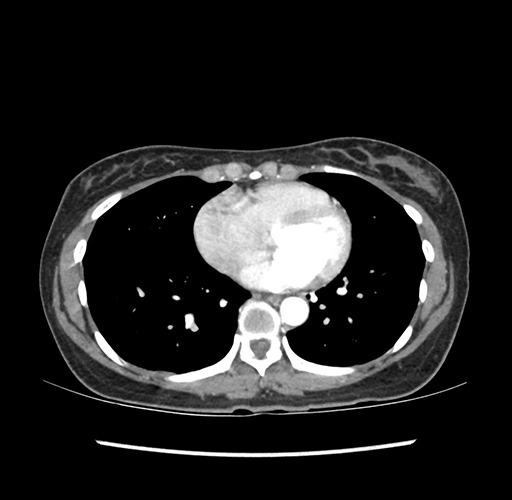

Imaging Analysis

Look through the patient's CT scan to identify any areas of concern for the necessary procedure.

Based on your CT findings, which issue(s) would give reason for "planned slowing down moment(s)" in this case?